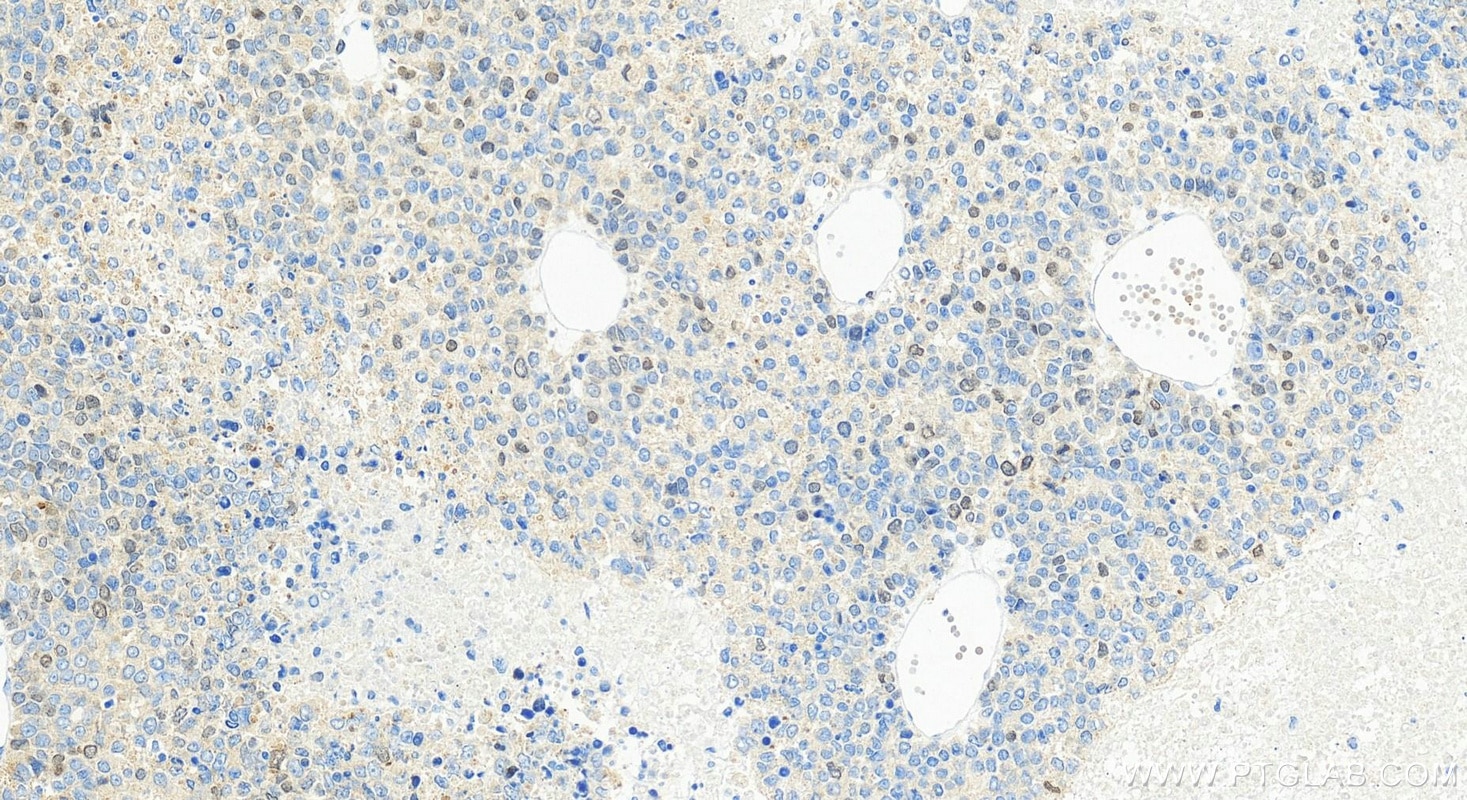

| Positive IHC detected in | Hepatocellular carcinoma tissue Note: suggested antigen retrieval with TE buffer pH 9.0; (*) Alternatively, antigen retrieval may be performed with citrate buffer pH 6.0 |

| Immunohistochemistry (IHC) | IHC : 1:200-1:800 |